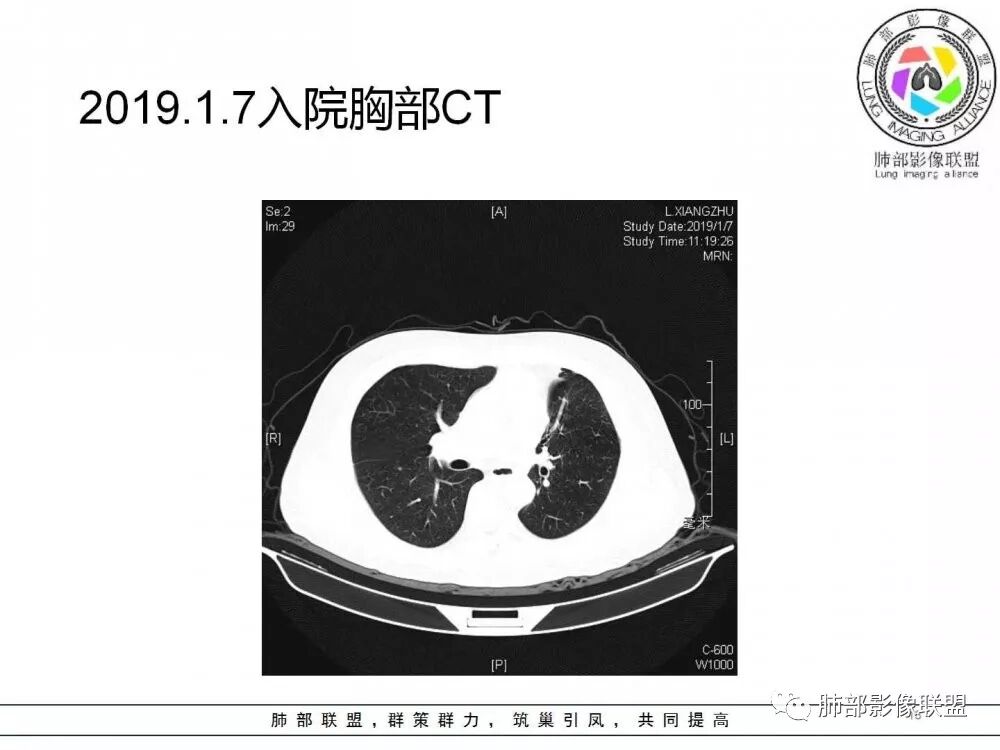

肺部病灶从2月份就开始有了,应该最早说是1月7号就有了,到3月13号稍微增大一点,到后面几乎就没变化了,到5月份好像稍微大一些,炎性肯定是炎性,就是这个炎性是到底什么病变呢?其实本没变化,它特点一个是在叶裂上,跟血管关系密切,但是病灶边缘稍收缩,病灶这么没有太大变化,我还是支持炎性病变。